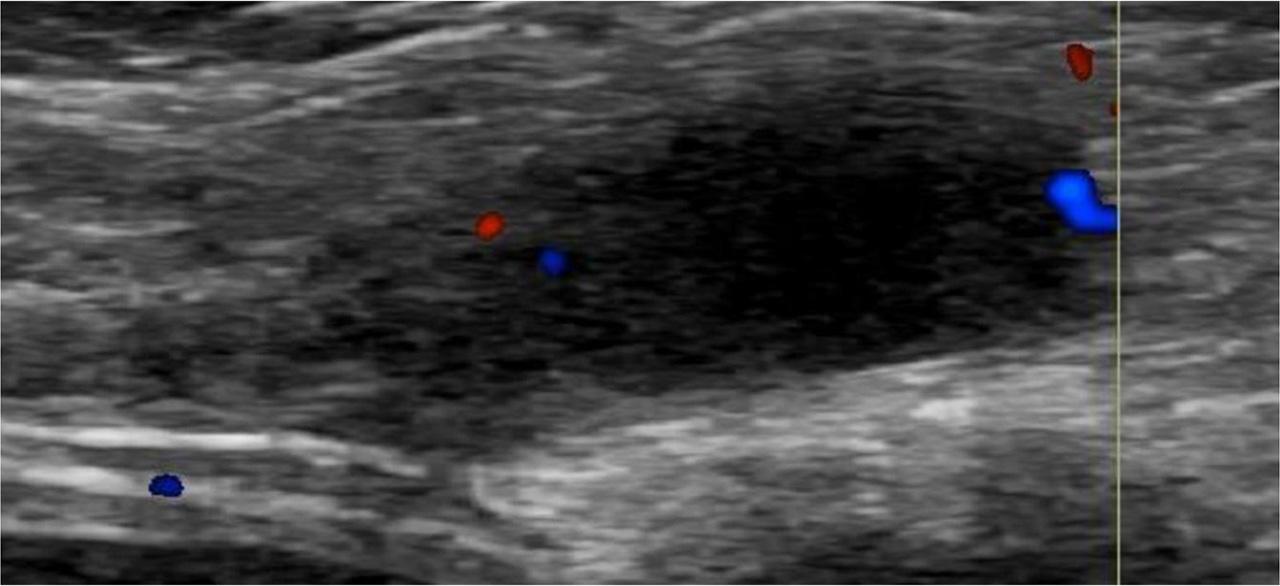

Ultrasound of the right groin was done, revealing a 2 × 1.9 × 1.4 cm fluid-filled superficial cystic lesion seen medial to the pubic bone at the level of the right superficial inguinal canal and 1.1 cm away from the deep inguinal ring (Fig. 1). No abnormal vascularity was depicted on color Doppler images (Fig. 2). The amount of fluid did not change with the Valsalva maneuver. No intervening bowel loops were seen. The left inguinal canal was normal. The rest of the examined abdominal viscera showed no abnormalities. The sonographic features were compatible with a hydrocele of the canal of Nuck. The patient was referred to the pediatric surgical clinic for consultation, where conservative management and observation were recommended, with surgical repair to be considered if any symptoms or complications should occur.

Color Doppler ultrasound image of the right groin showing a fluid-filled cystic lesion with no notable abnormal vascular uptake